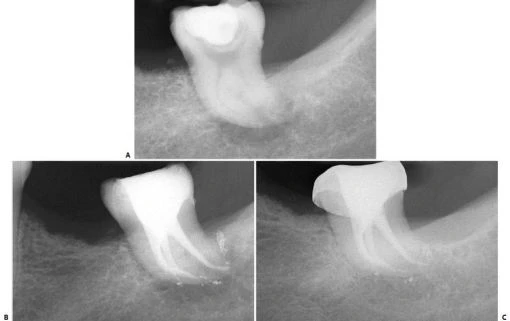

–  Trong 35% trường hợp có sự hiện diện của 4 ống tủy. Chân xa có 2 ống tủy, 1 ở phía ngoài và 1 ở phía trong (hình 11.109).

–  Ống tủy xa thứ 2 thỉnh thoảng được thấy ở 1 chân riêng biệt ở phía xa trong. Nó hơinhỏ hơn và nằm ở phía gần chân răng xa ngoài (hình 11.110).

Hình 11.109. A. Phim sau điều trị của  RCL 1 dưới. B. Nhìn theo chiều gần xa trên cùng răng đó có thể thấy có 2 ống tủy ở chân xa, các ống tủy chân gần mặc dù gặp nhau ở 1/3 giữa nhưng vẫn có 2 lỗ chóp. C. Xoang tủy ở R36 với 2 ống tủy ở chân gần và 2 ống tủy ở chân xa. D.Trong trường hợp răng cối lớn dưới khác cũng có 4 ống tủy, mỗi ống tủy có 1 lỗ chóp riêng.

Hình 11.110. A. Một vùng hơi cản quang trong vùng chẽ R36 vì chân xa ngoài. Dễ dàng nhận ra phần laminadura bao quanh chân răng này và hình ảnh ống tủy. B. Hình ảnh răng cối lớn một dưới sau khinhổ ra. C. Phim sau điều trị R46 với 2 chân xa và 2 ống tủy xa.